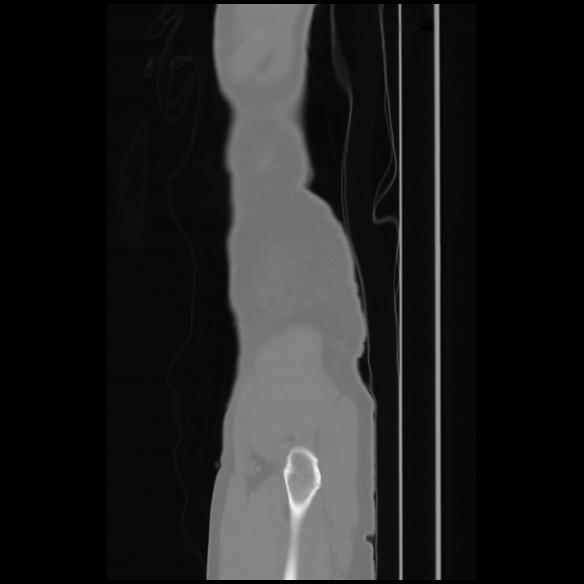

7 CUERPO,CE,Sagittal,3.000,CUERPO,Sagittal,